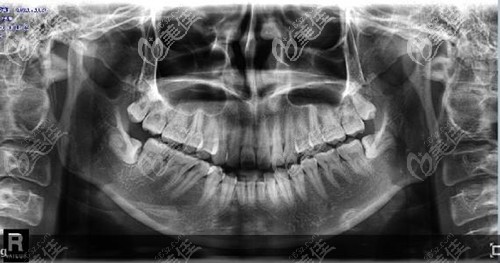

想必很多人多少都有牙齒問題,其中智齒是比較難決定要不要拔掉的,有人說我的智齒橫著長(zhǎng)七八年了也不疼,應(yīng)該沒事,其實(shí)這種才更應(yīng)該選擇拔掉。